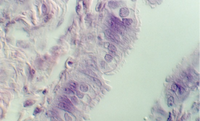

The cervix continues and joins with the vagina. The cervix is lined by simple high columnar epithelium which consists of mucous cells. These are shown in the following views. In the lowest magnification, one can see bundles of smooth muscle in the wall (see below)

Moving toward the vagina, one can see the abrupt transition between the cervical glands and the stratified squamous epithelium of the vagina. The region showing the vaginal and cervical areas juxtaposed is seen in the following photo.